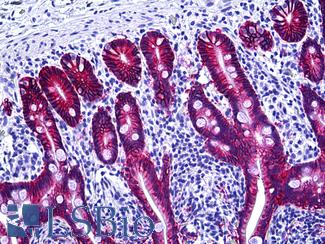

Anti-KRT20 / Cytokeratin 20 antibody IHC of human small intestine. Immunohistochemistry of formalin-fixed, paraffin-embedded tissue after heat-induced antigen retrieval. Antibody LS-B5959 dilution 1:50. This image was taken for the unconjugated form of this product. Other forms have not been tested.

CK7 (KRT7)

Anti-KRT7 / Cytokeratin 7 antibody IHC of human placenta. Immunohistochemistry of formalin-fixed, paraffin-embedded tissue after heat-induced antigen retrieval. Antibody LS-B7163 concentration 10 ug/ml.